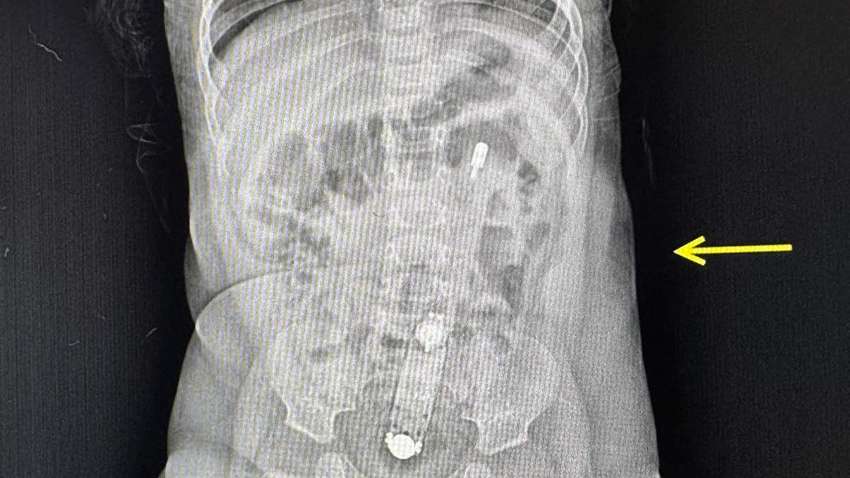

Рентген-снимок ребенка. Фото: Волынская больница

На рентгене был отчетливо виден термометр, также он пальпировался через живот. "Достать прибор было очень непросто", — рассказывает хирург и эндоскопистка больницы Юлия Артишук.